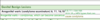

What are these radiographic findings?

Residual Cysts